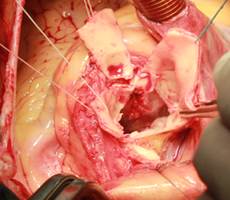

Sau khi gây mê toàn thân, bệnh nhân được mở ngực theo đường giữa xương ức, heparin toàn thân, tuần hoàn ngoài cơ thể ở nhiệt độ thường giữa động mạch chủ lên với 2 tĩnh mạch chủ, bơm dung dịch liệt tim trực tiếp 2 lỗ vành qua đường mở gốc động mạch chủ. Kiểm tra gốc động mạch chủ thấy áp xe toàn bộ vòng van lan xuống dưới vách liên thất. Nhiều mủ màu sô cô la trào lên từ vách liên thất. Cắt lọc toàn bộ khối áp xe vòng van động mạch chủ và một phần vách liên thất cho đến khi quan sát bằng mắt thường thấy tổ chức lành, không còn mủn nát và mủ. Kiểm tra van hai lá thấy có sùi lá trước kích thước bé 3 – 5mm, đứt dây chằng lá trước gây hở van nhiều, tổn thương chưa lan vào vòng van. Cắt bỏ van hai lá, bơm rửa làm sạch các buồng tim bằng nước muối sinh lý 9‰. Đóng gốc động mạch chủ lại bằng chỉ Prolene 5.0. Cắt mỏm thất trái một lỗ có đường kính 18mm rồi tiến hành làm miệng nối với ống mạch nhân tạo số 27. Một ống mạch nhân tạo số 27 khác có kèm theo van được nối với động mạch chủ xuống đoạn ngang mỏm tim. Sau đó hai đoạn mạch này được nối lại với nhau tạo thành một cầu nối có van nhân tạo giữa mỏm tim và động mạch chủ xuống. Thay van hai lá cơ học số 31. Hai lỗ động mạch vành được nối với động mạch chủ lên bằng những ống mạch nhân tạo đường kính 6mm (Hình 4). Sau khi đầy tim đuổi khí và thả cặp động mạch chủ, tim đập trở lại với tình trạng block nhĩ thất hoàn toàn. Đặt điện cực thượng tâm mạc và dẫn theo máy tạo nhịp để đạt tần số tối ưu. Ngừng máy tim phổi nhân tạo, rút các ống, trung hoà Heparin và đóng ngực theo giải phẫu.

Hình 4: a,b: Abscess toàn bộ gốc ĐMC lan xuống vách liên thất. c,d: Cắt mỏm thất trái rồi nối với ống mạch nhân tạo số 27. e: Nối ống mạch nhân tạo có van vào ĐMC ngực ở vị trí ngang mỏm thất. f,g: Nối hai đoạn mạch lại với nhau thành cầu nối có van giữa mỏm thất và ĐMC ngực. h: Nối ĐMC lên và các lỗ vành bằng ống mạch nhân tạo có đường kính 6mm.